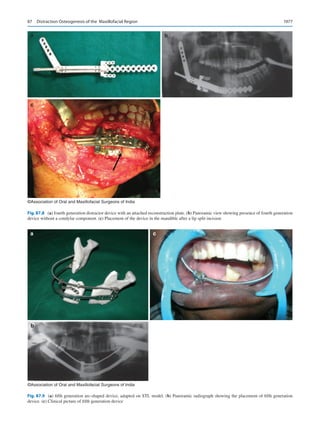

chemotherapy may be best effective for the management of

1  Oral and Maxillofacial Surgery in India: How Did We Get Here and Where Are We Going?

6

their cancers even before they see their doctor, today. Where